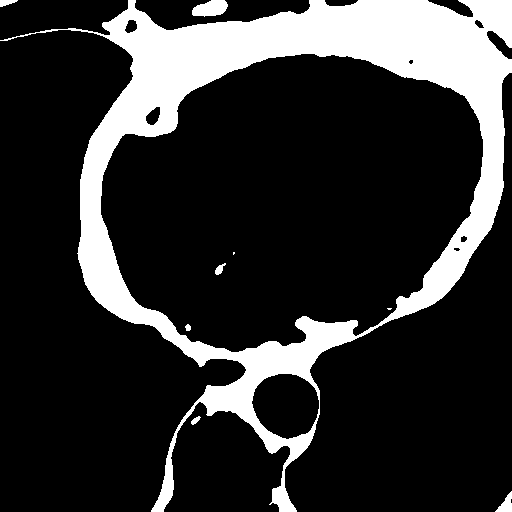

We extracted supervoxels, using the SimpleITK implementation of SLIC (Lowekamp et al., 2018), from the template images by configuring SLIC to place seeds at every 25:th voxel along each dimension, with spatial proximity weight set to 0.2, and forcing connectedness of the clusters. An example of the SLIC supervoxels computed for the template images is shown in Fig. 5. For each cluster, we computed the statistics of the density and JD images within each cluster. To reduce the effects of registration errors and effects of supervoxels containing tissues of different densities, we applied a filter where voxels with a density (HU) outside an interval given by the 1.5 IQR outlier detection method were excluded from the mean value calculation for both the density images and JD images.

Female

Male